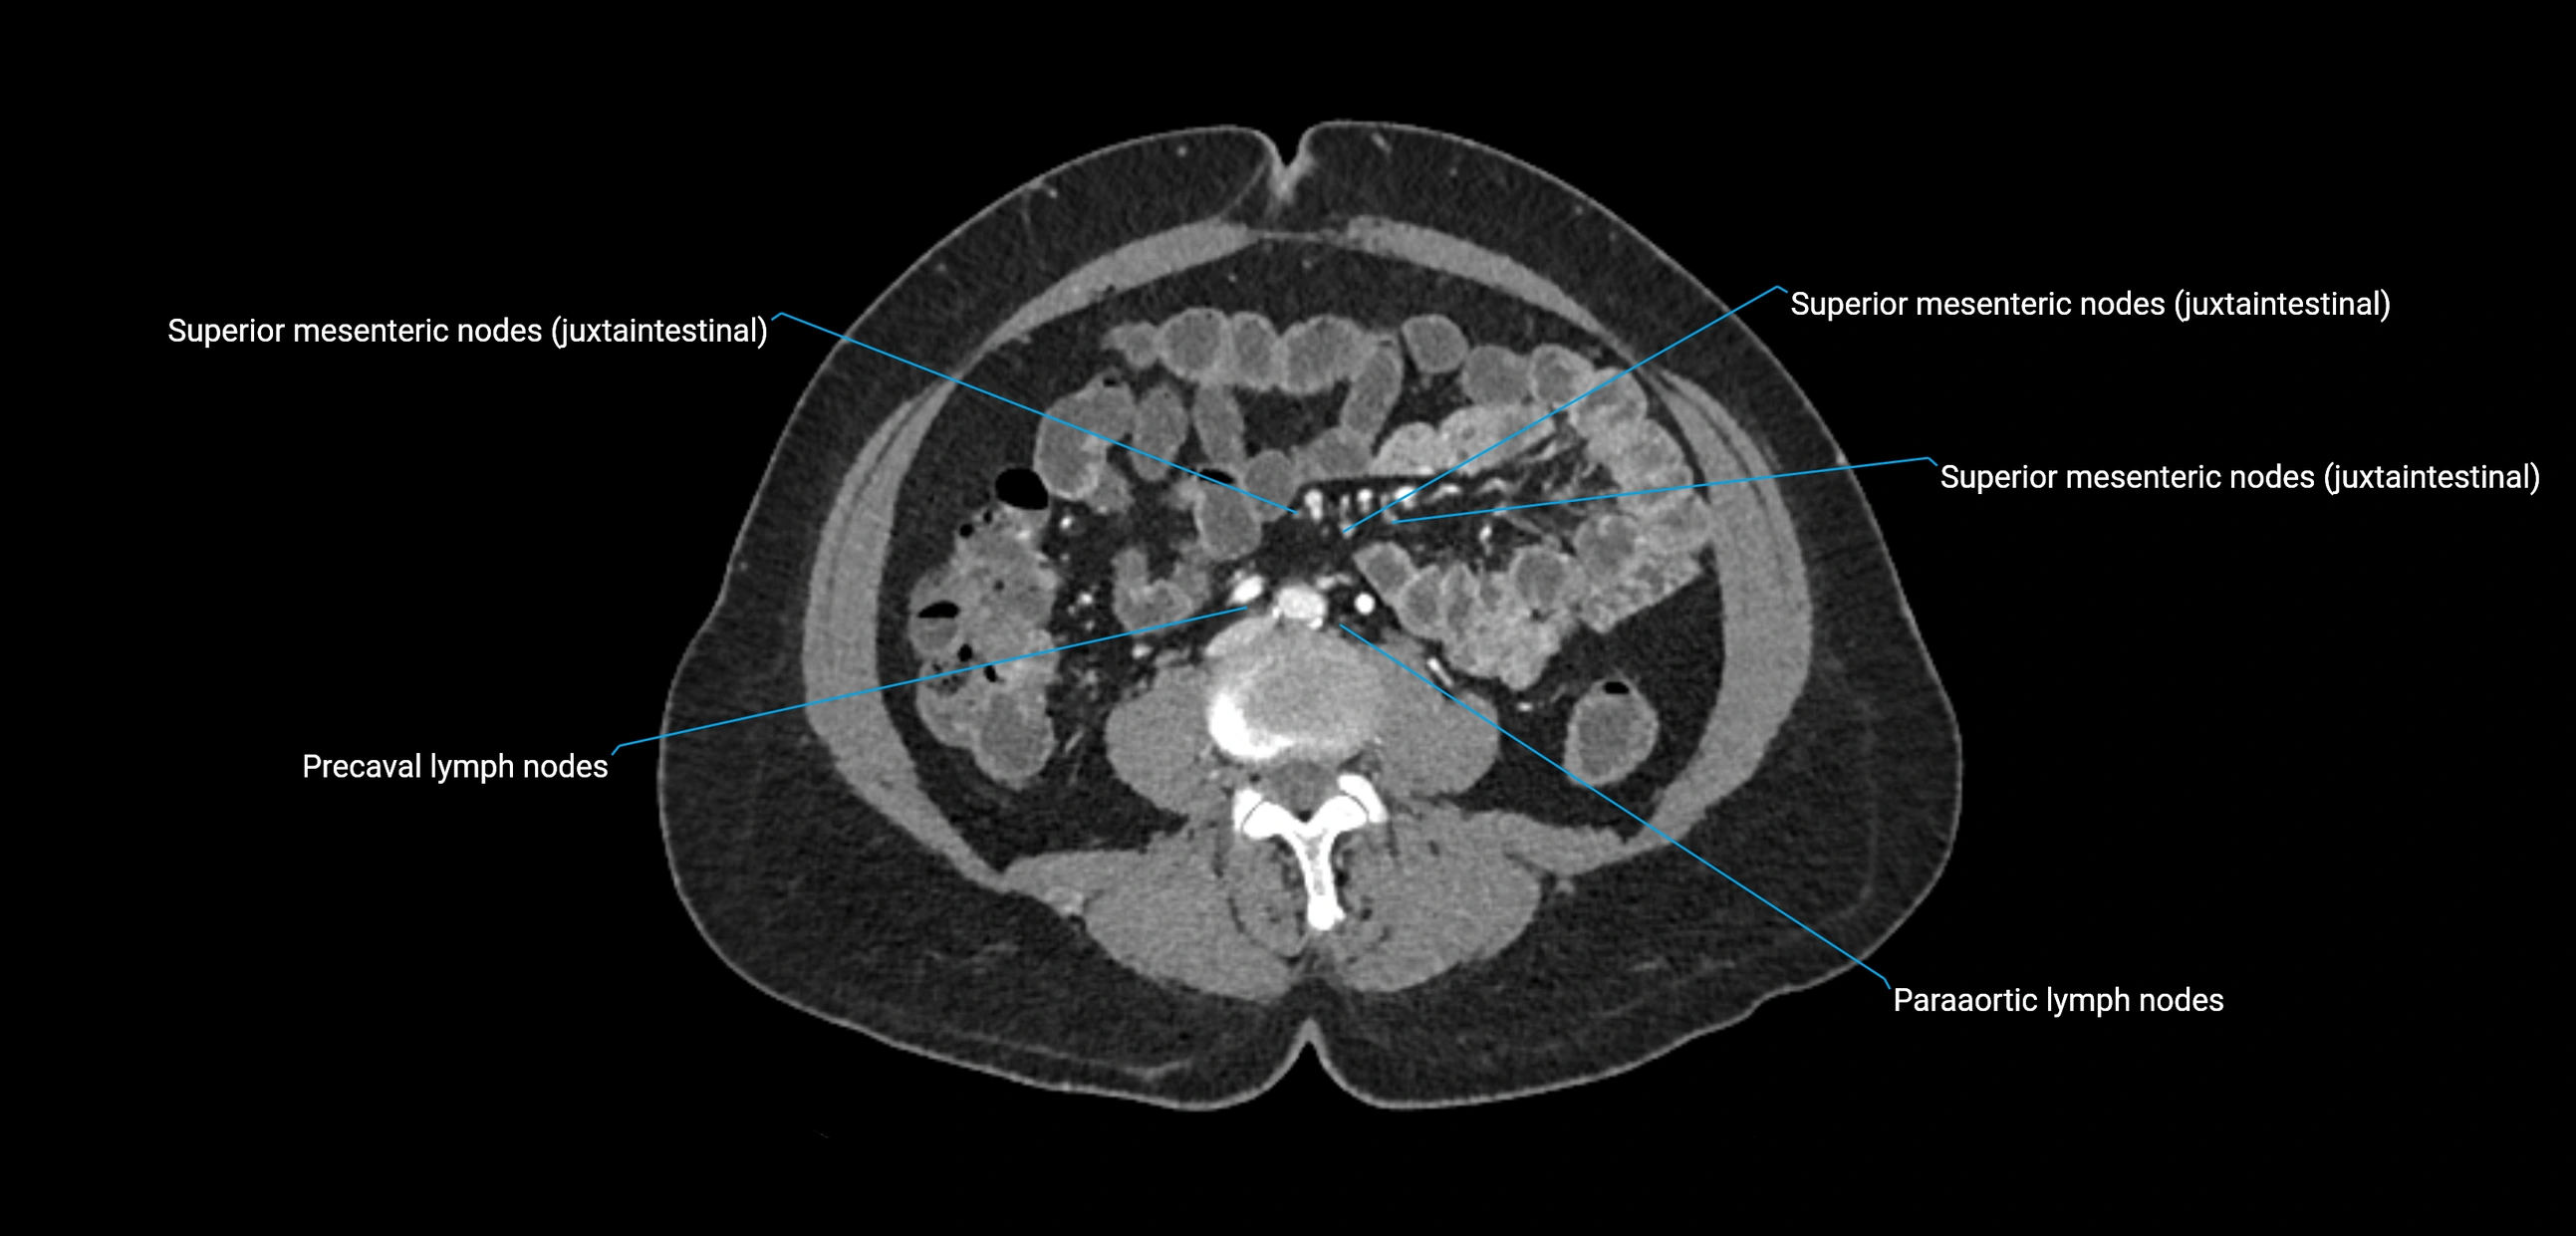

CT Appearance

CT Pre-Contrast:

• Nodes appear as soft-tissue density nodules adjacent to the aorta and IVC

• Calcification may be seen in chronic infections (e.g., tuberculosis)

CT Post-Contrast:

• Normal nodes enhance homogeneously

• Malignant nodes may show heterogeneous enhancement, central necrosis, or conglomerate formation

• Size >1 cm short axis is suspicious, though morphology and distribution are equally important